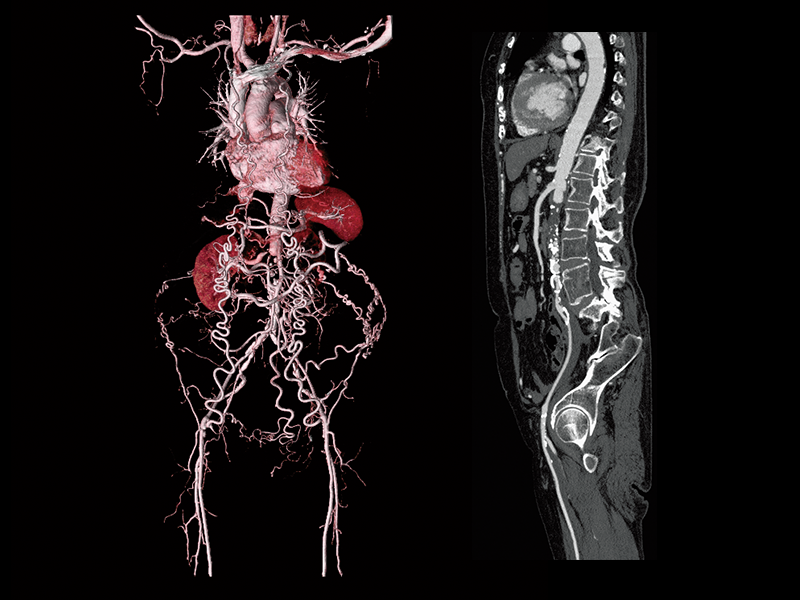

Abdominal aortic occlusion

Intraoperative oxygen desaturation(Left)

Left common iliac artery occlusion(Right)